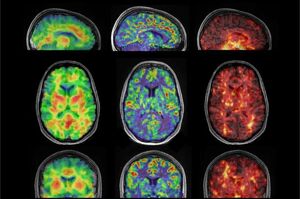

متخصصان مغز ۱۷ داوطلب بین ۲۲ تا ۳۵ سال را با استفاده از الاستوگرافی تشدید مغناطیسی (MRE) اسکن کردند. MRE که تصویربرداری تشدید مغناطیسی (MRI) را با امواج صوتی ترکیب میکند، اطلاعاتی را برای ایجاد تصاویر دقیق از سطوح مختلف سفتی در مغز به متخصصان ارائه میدهد.

متخصصان گفتند: ما از طریق MRE میخواستیم بفهمیم که چگونه جریان خون میتواند به طور بالقوه بر سفتی مغز تأثیر بگذارد. هیپوکامپ تنها بخشی از مغز است که این رابطه بین جریان خون و سفتی را نشان میدهد.